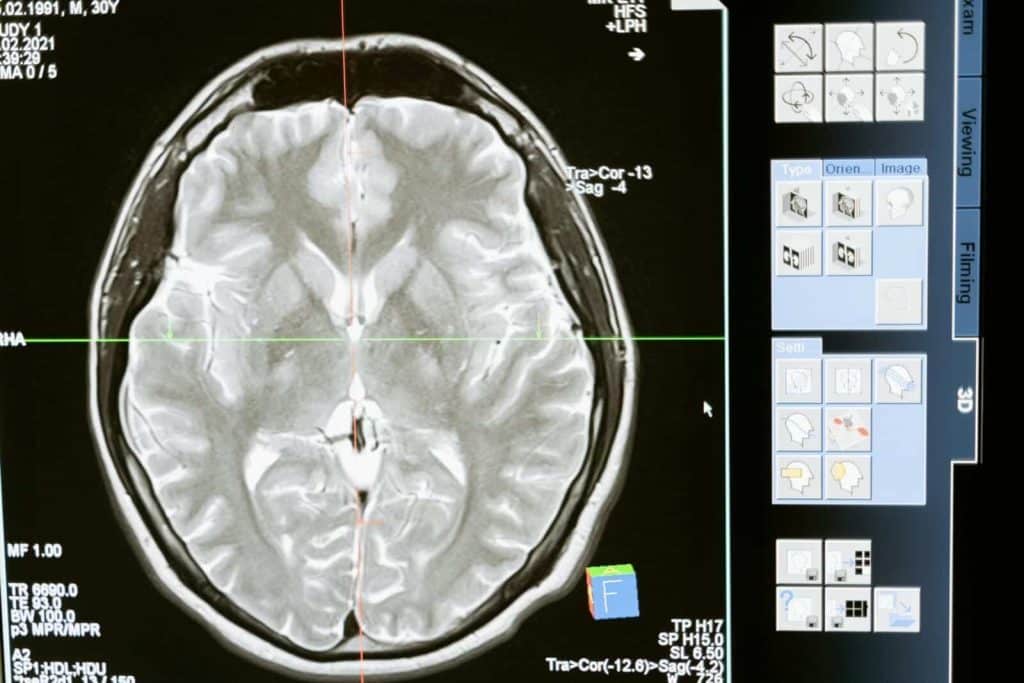

Intricate MRI brain scan displayed on a computer screen for medical analysis and diagnosis.